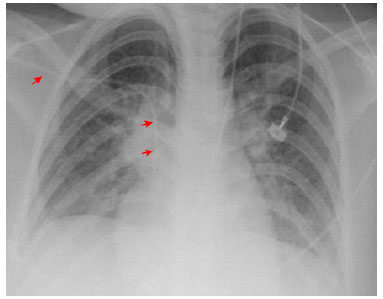

Physical Exam. Patient in poor general health, puffy face with expression of severe pain; BP 90/60 mmHg., RR 26 bpm., HR 134 bpm., temperature: 37.8 °C, oxygen saturation 95% on room air. Skin and mucous membranes: bilateral conjunctival injection with eyelid desquamation. Dry mucous membranes, erythematous fissured and bleeding lips; limitation of mouth opening due to pain, erythematous oropharynx. Erythematous rash morbiliforme involving over than 90% of body surface area with areas of sloughing of lips, nostrils, (Figure 2) and genitals. Soft pitting edema of the face, trunk, abdomen, and extremities. Respiratory, cardiovascular and abdominal system: without alterations, except for tachypnea and tachycardia. Neurological: sleepy, but oriented.

Figure 2 Day of admission (November 28, 2019). Morbilliform and erythematous rash involving more than 90% of the body surface with sloughing of the lips and nostrils (A-C). Bloated face; dry mucous membranes, erythematous, fissured and bleeding lips; and limitation of mouth opening (A-C).